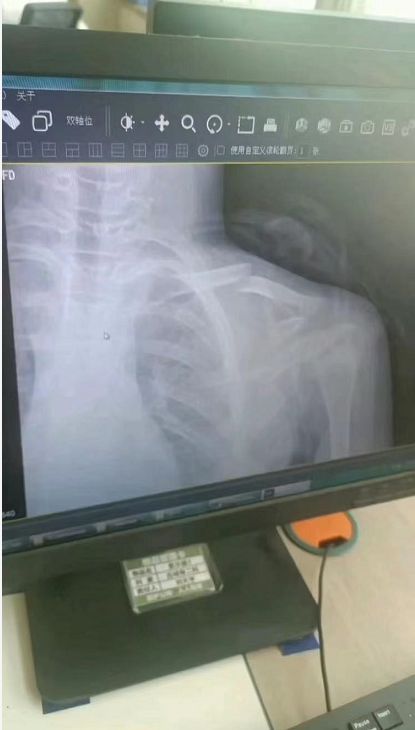

6月11日,莒县公安局刑侦大队技术中队出具伤情鉴定书,小孩左锁骨中段处3.4cm长斜形缝合创口,左胸锁骨关节处见1.2cm长斜形缝合创口,均系手术所致。据损伤特点分析,符合钝性外力所致,鉴定意见为损伤程度属轻伤二级。